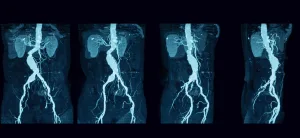

Aort Anevrizmasında Tanı Nasıl Konur